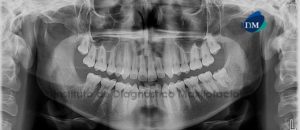

Paciente de sexo femenino de 32 años de edad acude al Instituto de Diagnóstico Maxilofacial para evaluación general de ambos maxilares. A la evaluación panorámica